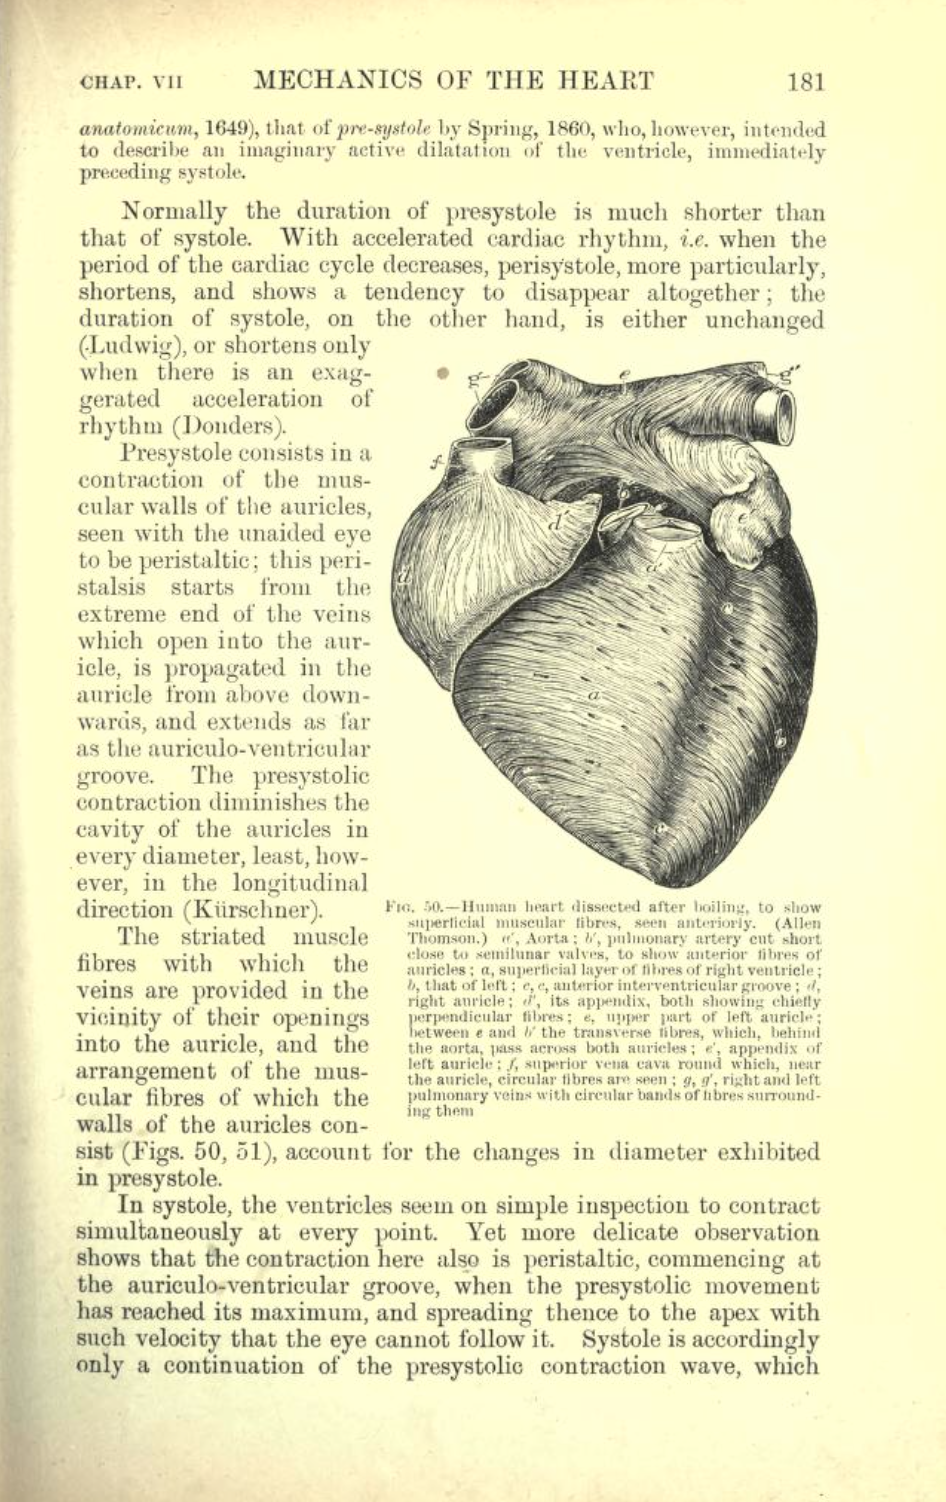

“William Harvey (1578-1657), who founded modern experimental physiology, was the first to establish not only the fact of the circulation but also the physical laws governing it, and is commonly reckoned the Father of Modern Medicine. He owed his interest in the movements of the blood to Fabricio, his tutor at Padua, who drew his attention to the valves in the veins, thus suggesting the idea of a *circular* as opposed to a to-and-fro motion. Harvey’s great generalisation, based upon a long series of experiments in vivo, gave the coup de grâce to Galenic physiology.

De Motu Cordis : Anatomical Studies on the Motion of the Heart and Blood - 1628 - William Harvey (complete text)

Re: William Harvey

In 1599, aged 21, he enrolled at the University of Padua in Italy, which was acclaimed for its medical and anatomy courses. (Interestingly, when Harvey arrived in Padua, Galileo Galilei had already been there for seven years, teaching mathematics, physics and astronomy.)

The greatest influence on Harvey at Padua University was his teacher, Hieronymus Fabricius, who was a skilled anatomist and surgeon. The two became friends and Harvey learned from Fabricius that dissection offered a route to better understanding of the human body.

Harvey made his discoveries because he ignored the conventional wisdom of medical text books, preferring to make his own observations and form his own conclusions when he dissected animals.

Remarkably, western medical beliefs and theories about blood and circulation had advanced little since Galen wrote his medical textbooks in Rome 1400 years earlier.

“The ancient world and the Middle Ages had no idea of the existence of the circulation of the blood. It was not until the Late Renaissance that efforts were made to grasp this process anatomically and understand its function. Thus, Miguel Serveto searched in vain for a connection between the right heart and the left, and in so doing discovered the lesser circulation in 1553. In 1569, Caesalpinus traced the path of the large circulation. Jacobus Sylvius (1543), Canani (1564), and Fabricius of Aquapendente (1574) concurred in recognizing the centripetal movement of the venous bloodstream from the structure and arrangement of valves in the veins. Before their time it had been believed that blood flowed outwards to the periphery, even in the veins.

“William Harvey, one of the most gifted pupils of Fabricius (1578-1657), combined all these individual findings with the results of his own research to form the general picture of what we today call the circulation of the blood. But even he had no clear idea of the circulation in the region of the capillaries. This section was explained and described for the first time by Malpighi in 1661, after he had viewed a frog's lung under a microscope.

“In any event, it is the year 1628, in which Harvey published his classic work De motu cordis et sangunis, that we can call the birth-year of cardiology.”